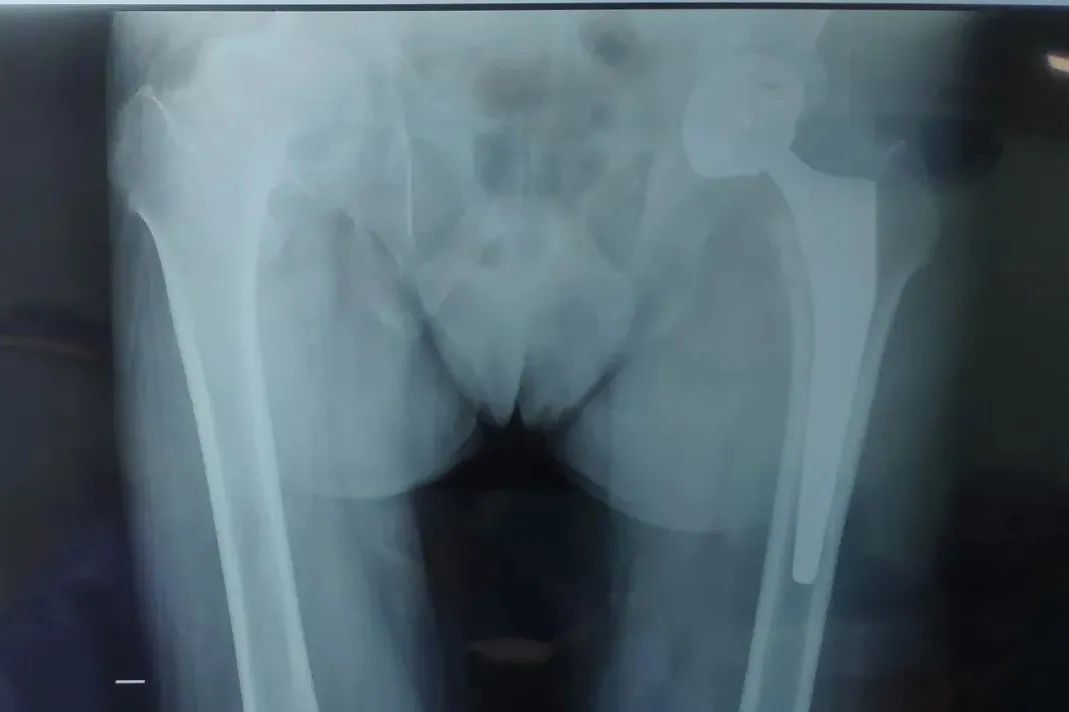

4月24日,71歲的賈大爺因髖部疼痛難忍,活動受限,家人帶其來到鄭州西區(qū)中醫(yī)院骨科找到總院幫扶我院的骨科首席專家王上增教授(河南中醫(yī)藥大學(xué)骨傷學(xué)院副院長)。

手術(shù)如期進行,手術(shù)過程中王上增教授說到:“患者選擇再次來到我們醫(yī)院,是對于我們的信任,這就是對我們的肯定和嘉獎。要把每一次手術(shù)都當(dāng)成是上戰(zhàn)場,做一臺手術(shù),造一個口碑;挽救一個患者,造福一個家庭。”

術(shù)后無不良反應(yīng),并于術(shù)后第三天可下床行走。